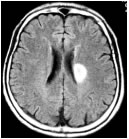

脳梗塞とは脳の血管が詰まって神経細胞が死んでしまう病気です。神経細胞は一旦死ぬと生き返ることはありません。脳の各部位は「見る、聞く、話す、身体を動かす」などの様々な機能を分担しています。神経細胞が死ぬと、その部分の脳の機能が損なわれます。そのため、脳梗塞を起こすと様々な症状(片麻痺、感覚障害、言語障害、意識障害など)が現れたり、後遺症が残ることがあります。

| ラクナ梗塞 | アテローム血栓性脳梗塞 | 心原性脳塞栓症 |